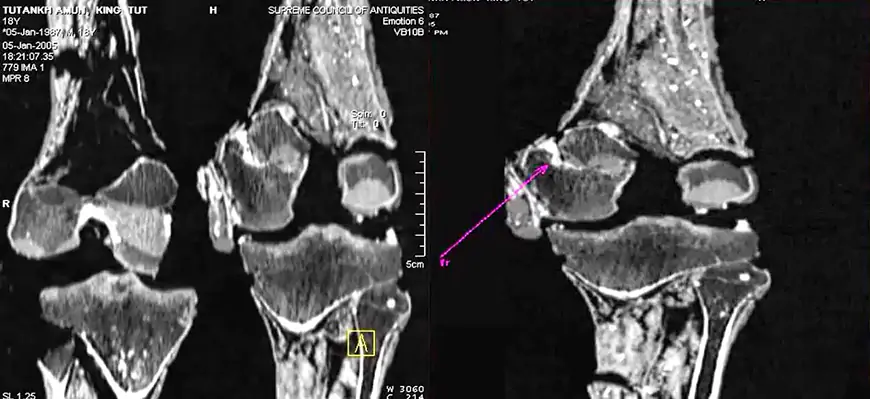

Quizás la teoría más popular es que Tutankamón fue asesinado. Esta teoría fue popularizada por el renombrado egiptólogo Robert Brier, quien argumentó que el daño en la parte posterior del cráneo de Tutankamón encontrado en una radiografía de 1968 era consistente con un golpe fatal en la parte posterior de la cabeza. Brier teorizó que Tutankamón fue asesinado por algún agente siniestro que creía que el joven rey estaba interfiriendo con sus propios planes.

La teoría del asesinato es popular, pero tiene sus inconvenientes. Exámenes más detenidos de la momia en 2005 y 2016 revelaron que el daño en la parte posterior del cráneo no fue un golpe fatal, sino un efecto secundario del proceso de momificación. El propio Bryer estuvo inmediatamente de acuerdo con este punto de vista y admitió que la teoría del “golpe en la cabeza” había sido refutada. Brier dice que las pruebas circunstanciales respaldan el asesinato, pero ahora sospecha que se cometió por otros medios. Por ejemplo, veneno o alguna otra lesión que la momia aún no ha detectado, pero no hay evidencia física concluyente que respalde tal teoría por el momento.

Hay tres pruebas físicas de ello: falta de costillas, una pierna rota y falta de corazón. Se afirmó que el pecho y el corazón de Tutankamón sufrieron daños irreparables en el accidente, que también lo dejó con una pierna izquierda rota. El trauma físico causado por esta lesión ciertamente habría sido fatal y, si no hubiera muerto en el impacto, se habría desangrado en cuestión de minutos.

Hay algo que plantea la teoría del choque del carro que está provocando más especulaciones: Tutankamón tiene una fractura compuesta en su pierna izquierda. La presencia de líquido de embalsamamiento dentro de la lágrima y la falta de signos de curación sugieren que la lágrima se produjo poco antes de su muerte y nunca tuvo tiempo de sanar. Esta es la proverbial prueba irrefutable.